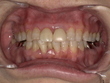

Before(治療前)

転倒の衝撃により、上の前歯の被せ物(クラウン)が外れ、歯の大部分が欠けている状態でした。

このままでは見た目の問題だけでなく、噛む力によって歯がさらに割れる可能性もあり、早期の治療が必要な状態でした。